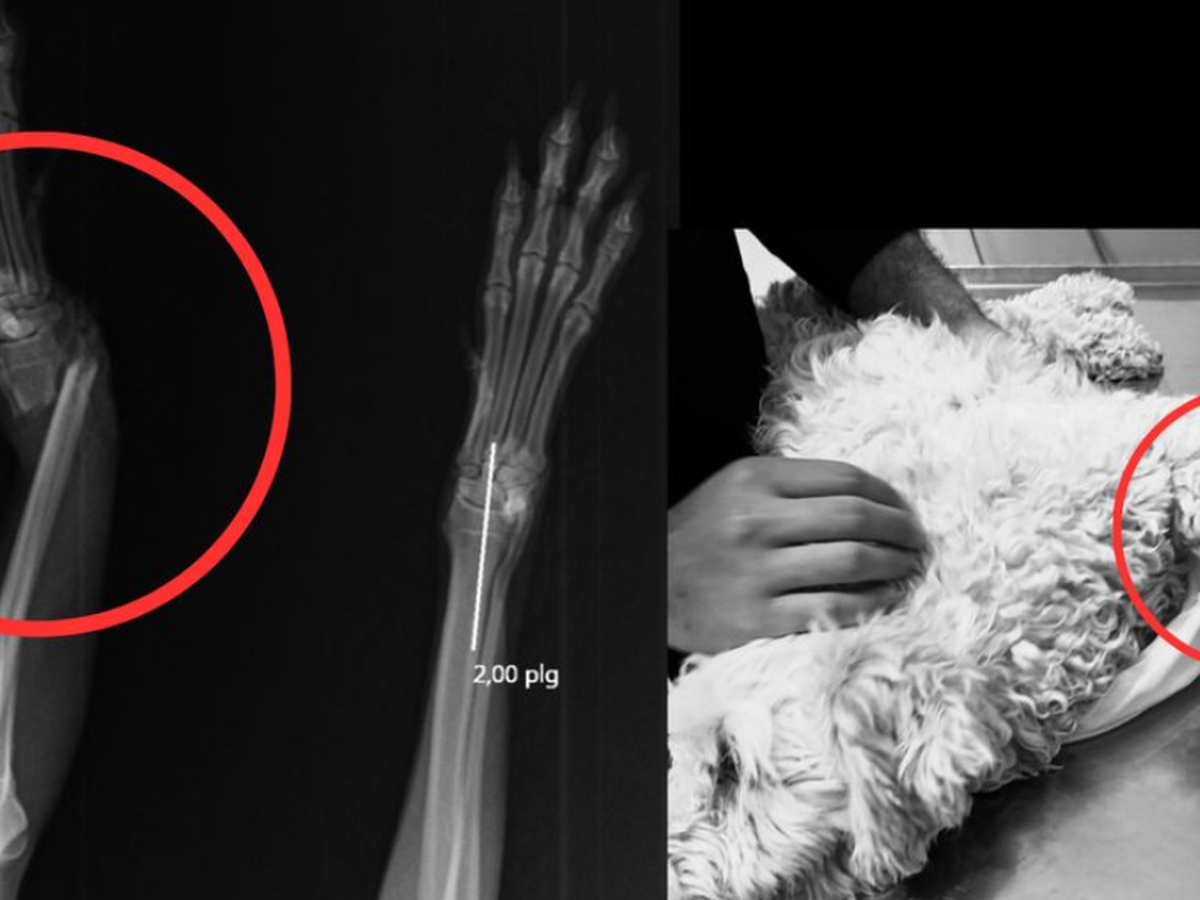

Hola me llamo Milka, me fracture la pata saltando del balcón de mi casa y al momento de caer tuve una fractura expuesta.

Podía perder mi pata y que me la amputaran, pero afortunadamente, me la dejaran con una placa.